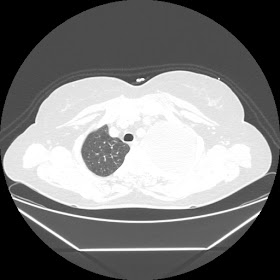

A 45 years old woman recurrent HRCT Images